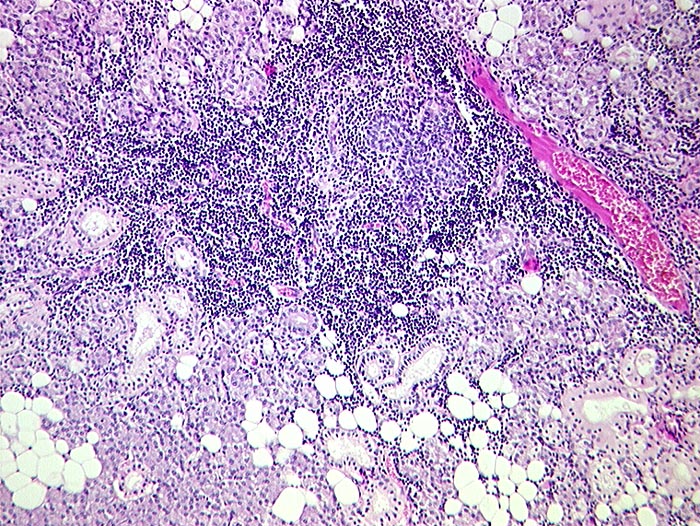

Autoimmun- Sialadenitis bei Sjögren Syndrom

Parotis

Das Zellbild ist je nach Stadium mehr oder weniger zellreich und zusammengesetzt aus Lymphozyten, Myoepithelien und selten Azinuszellen. Ein lymphozytäres Zellbild ist in Kombination mit dem typischen klinischen Bild (Keratokonjunktivitis sicca, Xerostomie, rheumatische Erkrankung) für die Sicherung der Diagnose ausreichend. Auf die Lippenbiopsie kann in diesem Fall verzichtet werden.